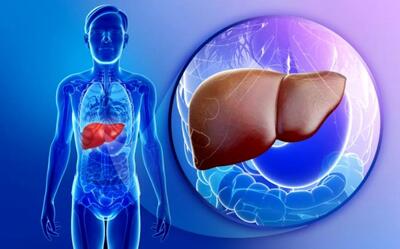

هشدار درباره همهگیری خاموش کبد چرب

کبد چرب به یکی از بیماریهای شایع در میان مردم تبدیل شده و آمارهای رسمی نشان میدهند که ۴۰ تا ۵۰ درصد از افراد به درجاتی از این بیماری مبتلا هستند.